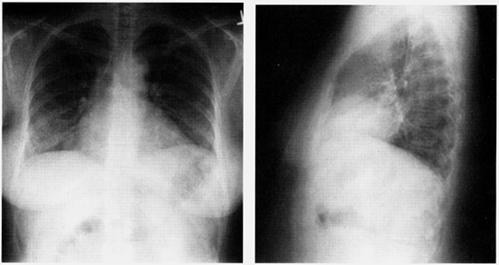

Imagine Rx de pericardita acuta

Semne radiologice cardiopulmonare:

cardiomegalie importanta cu contururi net trasate, stergerea arcuatiei normale, cord 'in carafa',

circulatie pulmonara normala.

radiologic: cord de dimensiuni normale cu contur net trasat, eventual cu calcificari pericardice si circulatie pulmonara normala,